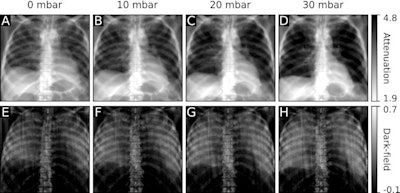

With higher pressure, the segmented lung area had higher visual and quantitative signal intensity on both dark-field and attenuation images, the investigators found. Overall, dark-field signal intensities at the same pressure were higher at later cycles.

Specifically, dark-field signal intensity was lower when pressure changed from 0.0 kPa to 1.0 kPa (0.00 psi to 0.15 psi) and thereafter, it followed the same pattern as that of the entire lung. Moreover, the attenuation signal behaved opposite to the dark-field signal, with a lower signal at higher pressures and later cycles, the researchers found.